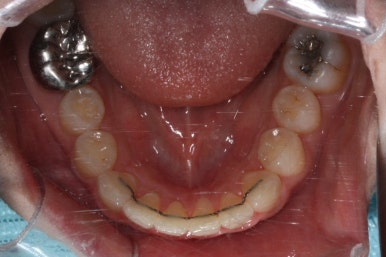

부산앞니교정 키다리아저씨치과에 처음 내원하셔쓸 당시의 입안 모습입니다.

앞니가 살짝 삐뚤어진 것을 볼 수 있고, 삐뚤어진 사이에서 약간의 틈새도 있었습니다.

예전에 치료 받으셨던 앞니 부분에 약간의 변색도 와서 미적으로 좋지 못한 상황이였습니다.